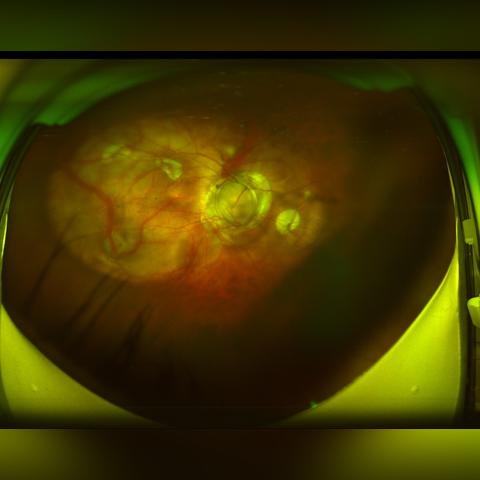

眼球震颤是一种常见的眼科疾病,表现为眼球的不自主颤动,严重影响患者的视觉质量和生活质量,随着医学科技的不断发展,眼球震颤的治疗方法也在不断更新和改进,本文将详细介绍眼球震颤的最新治疗方法及其具体数据。

眼球震颤的成因复杂多样,包括先天性眼病、神经系统疾病、视觉障碍等,主要症状表现为眼球不自主颤动,影响视觉清晰度和稳定性,部分患者可能伴随头痛、视力模糊等症状。